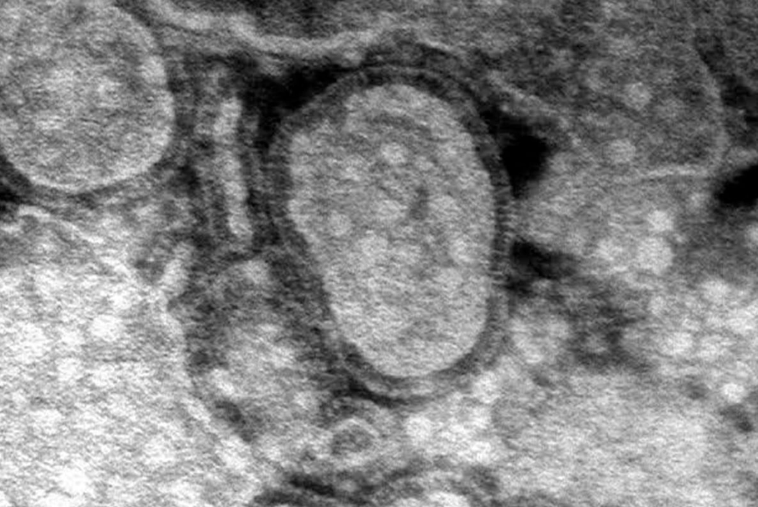

Cinco años después de la pandemia de Covid-19, China enfrenta un brote de metapneumovirus humano (HMPV), otra enfermedad respiratoria. Según informes y publicaciones en redes sociales, el virus se está propagando rápidamente y algunos afirman que los hospitales y crematorios están desbordados. Videos compartidos en línea muestran hospitales abarrotados, y algunos usuarios indican que múltiples virus, como la influenza A, el HMPV, Mycoplasma pneumoniae y Covid-19, están en circulación.

Se ha especulado que China ha declarado el estado de emergencia, aunque esta información no ha sido confirmada. Se sabe que el HMPV causa síntomas similares a los de la gripe y puede generar signos parecidos a los del Covid-19. Los funcionarios de salud están siguiendo de cerca la situación mientras el virus continúa propagándose.